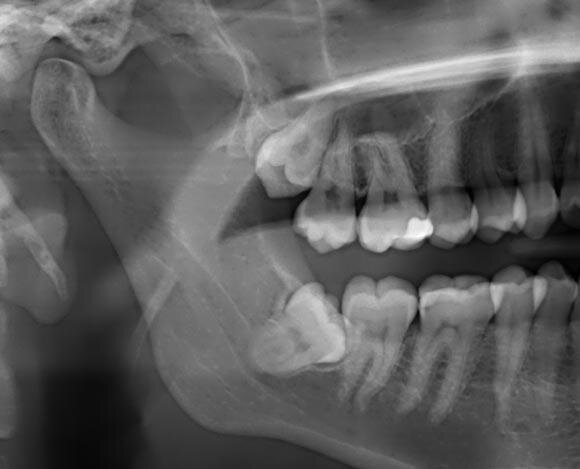

· маляр растет под углом, мешает другим зубам и доставляет дискомфорт, возрастающий во время еды;

Показания для хирургического вмешательства:

· зуб частично или полностью разрушен;

· прорезывание зуба стало причиной лицевой невралгии;